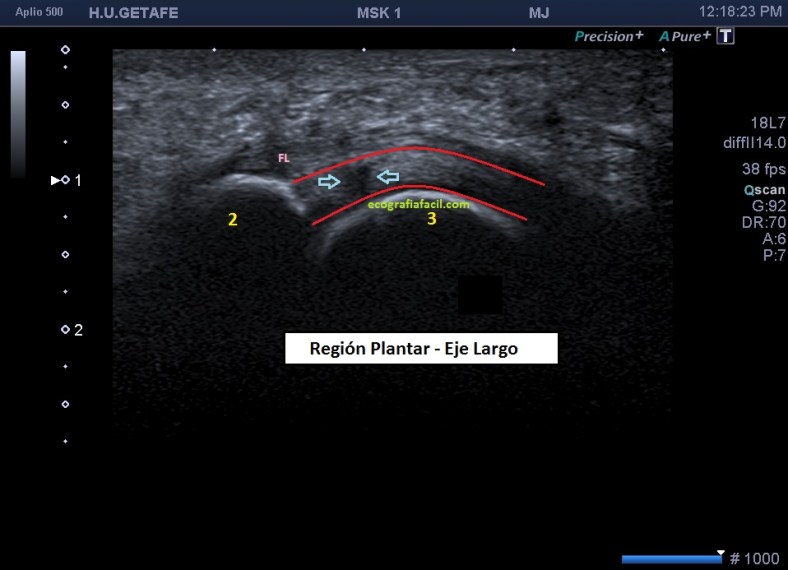

Estudiamos y demostramos la lesión o la normalidad en dos proyecciones, imagen 6, eje largo y eje corto de la zona y podemos comparar siempre con el lado contralateral, previsiblemente sano, dicho todo este conglomerado de ideas…las imágenes:

Marcadas con flecha azul puedes ver un efecto de discontinuidad a nivel de la placa plantar, hipoecogénico e irregular, demostrado en dos proyecciones.